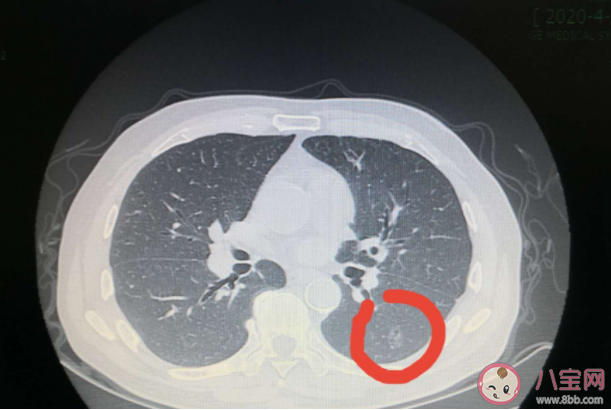

肺癌是一種高發(fā)癌癥,很多時(shí)候發(fā)現(xiàn)就是晚期了,有人在體檢的時(shí)候發(fā)現(xiàn)肺磨玻璃結(jié)節(jié),那么,會(huì)演變成肺癌嗎?什么是肺部磨玻璃結(jié)節(jié)?下面八寶網(wǎng)小編就帶來(lái)介紹。

體檢若發(fā)現(xiàn)肺磨玻璃結(jié)節(jié),其中80%不會(huì)演變成癌,但肺結(jié)節(jié)直徑越大,其惡性的可能性及惡性程度越高。醫(yī)生提醒,早期發(fā)現(xiàn)對(duì)防治肺癌、提高治愈率最為關(guān)鍵,40歲以上人群最好每年進(jìn)行一次檢查。

肺部磨玻璃結(jié)節(jié)有良性病變和惡性腫瘤兩種區(qū)別的,并不是一提到磨玻璃樣變就一定會(huì)是惡變。良性病變包括肺部炎癥、真菌感染、炭末沉積等,惡性腫瘤就是肺腺癌。

發(fā)現(xiàn)肺部磨玻璃結(jié)節(jié),更重要的是要考慮結(jié)節(jié)大小,一般來(lái)說(shuō)8mm以下的話,可以暫時(shí)不用考慮手術(shù)治療。

腫瘤性肺部磨玻璃結(jié)節(jié)是否選擇手術(shù),取決于該結(jié)節(jié)所處的病理階段:微小浸潤(rùn)腺癌、浸潤(rùn)腺癌建議手術(shù)治療。

首次查到肺部磨玻璃結(jié)節(jié)以后,除了積極治療之外,定期復(fù)查也很關(guān)鍵,如果有大小、形態(tài)、密度的改變,請(qǐng)及時(shí)就醫(yī)。